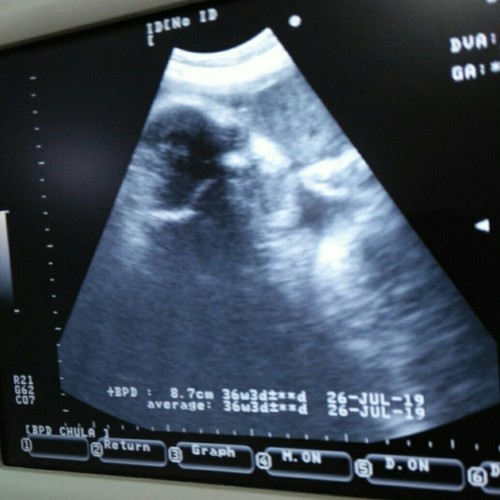

บ้านนี้ 14 สิงหาคะ คิดว่าน่าจะไม่ถึงสิงหาคะ มีอาการเจ็บท้องและท้องแข็งปั้นบ่อยมาก ไปหาหมอหมอบอกว่าอีกนานกว่าจะครบกำหนดคลอด หมอเลยฉีดยาระงับไว้ก่อนคะ

33+5ค่ะ กำหนดคลอด14 สิงหาคม แต่คิดว่าคงไม่ถึงเริ่มมีเจ็บๆหน่วงๆมท้องบ้างแล้ว น้ำหนักลูกไปหาหมอวันจันทร์ที่ผ่านมา 1.7 กก.

32+2 W กำหนด 24 สิงหาค่ะ ไปหาหมอเมื่อพฤหัสที่ผ่านมานน. 1989 แล้วค่ะตอนนี้เวลาเดินหน่วงๆค่ะน้องกลับหัวแล้ว

32+3 วีคค่ะ ท้องเล็กเหมือนกันค่ะ ซาวน์ล่าสุด 32 วีคน้องพึ่งน้ำหนัก 1,329 กรัมเองค่ะ

32+3wไปหาหมอเมื่อวันเสาร์ที่ผ่านมา น้ำหนักน้อง3,200 กำหนดคลอด24สิงหาจ้า

14สิงหาค่ะ ท้อง2แล้ว ท้องเล็กมากค่ะ กังวนว่าลูกจะตัวเล็กหรือป่าว

กำหนดคลอด 24 ส.ค ค่ะ วันนี้ไปหาหมอ นน.น้อง ประมาณ1,800 แล้วค่ะ